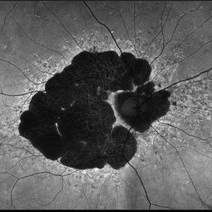

B-FAF in Stargardt's Disease

B-FAF in Stargardt's Disease

Jul 4 2024 by Tejaswita Verma

Blue fundus autofluorescence showing hypoautofluorescence picture of a 28 year old male with 6/60 vision in BE in a case of Stargardt's disease.

Photographer: DR. TEJASWITA VERMA

Imaging device: MIRANTE

Condition/keywords: fundus autofluorescence (FAF), hereditary macular dystrophy, Stargardt disease